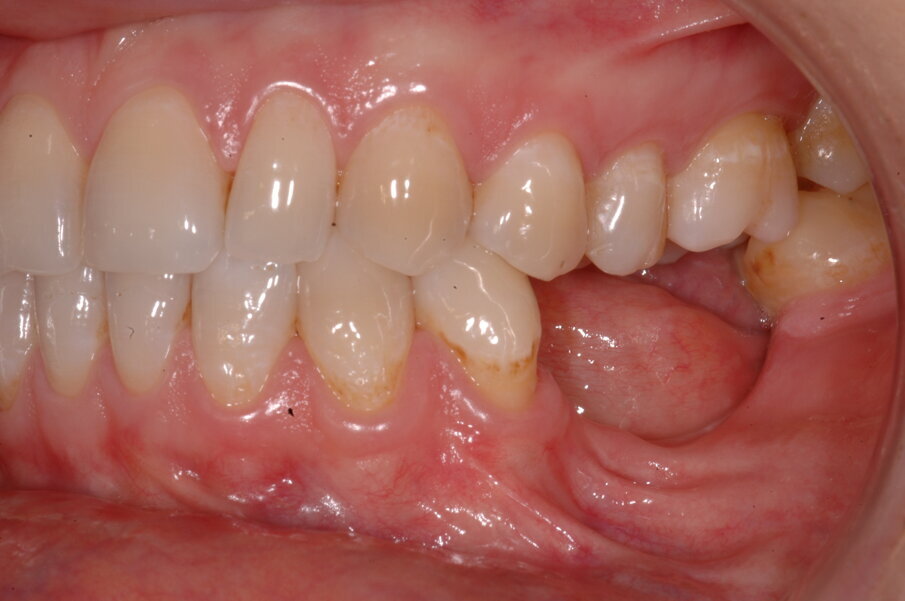

Una paziente di 35 anni si presentò alla nostra attenzione per risolvere un edentulismo parziale nella zona mandibolare inferiore sinistra conseguente all’estrazione traumatica degli elementi 35 e 36 in età scolare (Fig. 1). La paziente all’esame obbiettivo dimostrava un ottima igiene orale con un indice di placca del 7% e un indice di sanguinamento del 5%. L’esame clinico della zona traumatizzata evidenziava una lesione di terza classe di Seibert6 laddove il deficit osseo era caratterizzato da una deficienza nei tessuti duri e molli sia in senso orizzontale che in senso verticale. Risultava significativa anche la scarsa quantità di gengiva cheratinizzata a ricoprire la cresta residua, quantificabile in una banda larga non più di 2 mm (Fig. 2). Una volta eseguita la terapia causale atta a rimuovere il biofilm presente e a preparare la paziente per l’intervento, si procedette a eseguire un esame Cone Beam per approfondire la conoscenza dell’anatomia locale e procedere con un piano di trattamento adeguato alla soluzione di questa problematica.

Nella rx si vedono i due impianti con le viti di guarigione ad integrazione avvenuta. In figura 16 si nota l’ottimo aspetto dei tessuti peri-implantari con una adeguata quantità e qualità di gengiva cheratinizzata e le susseguenti corone in metallo ceramica successivamente cementate su due perni moncone in titanio fresati in laboratorio. Nelle foto successive si possono evidenziare le differenze dalla situazione iniziale (Fig. 17) a quella finale, in questo caso una foto di follow up a 48 mesi dalla finalizzazione del caso (Fig. 18). La rx a quattro anni dalla finalizzazione protesica evidenzia una situazione di perfetta stabilità, una cresta ossea ben mineralizzata ed un livello osseo inalterato dal momento della consegna del manufatto protesico definitivo (Fig. 19).